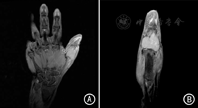

例2 患者男,53岁,于2013年3月7日因咳嗽咳痰伴发热半月就诊我院。入院后,行胸部CT检查提示,右上肺肿瘤性病变伴右上肺不张。纤维支气管镜取活检,病检结果示,右上肺鳞状细胞癌高分化型。考虑患者肺部肿块包裹大血管,暂不宜行手术,建议先行化疗,寻找手术机会。遂于2013年3月16日开始行吉西他滨联合奈达铂方案化疗3个周期。2013年6月21日开始行肺部病灶放疗,每次2 Gy,每周5次,共给予60 Gy,同时给予紫杉醇联合奈达铂每周同步化疗4个周期。期间出现放射性食管炎及Ⅲ度骨髓抑制,给予抗炎、激素、保护咽部黏膜、升白细胞和血小板等对症支持治疗。复查下颈部及胸部CT提示,肺部病灶较前缩小,余未见明显异常。后行紫杉醇联合奈达铂化疗2个周期,末次化疗时间为2013年11月27日。2013年12月16日,患者出现面部轻微水肿,胸部CT提示疾病进展,并右侧胸腔积液、肺部感染,遂行腹腔穿刺引流,同时口服替吉奥抗肿瘤治疗。2014年3月,患者感右手拇指肿胀疼痛,手部磁共振检查示,右侧拇指软组织肿胀,骨异常信号,考虑转移性病变(图3)。手部病灶行穿刺细胞学检查示转移性癌细胞(图4)。于2014年3月14日行右手拇指转移灶放疗,每次2 Gy,每周5次,共给予60 Gy,右手掌骨疼痛缓解后出院。虽经右手指骨放射治疗,局部疼痛消失,但因患者为肺癌晚期,且合并严重肺部感染,于6月27日死亡。